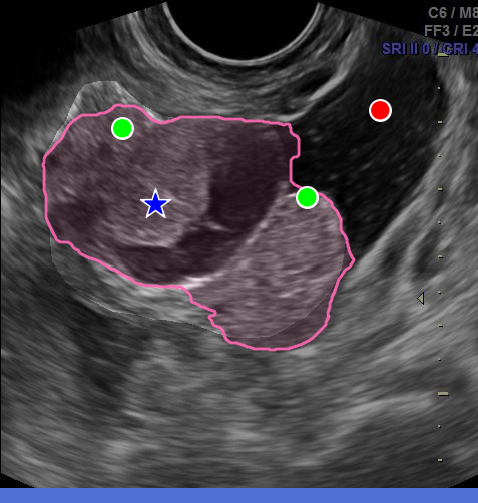

However, in the medical domain, overlapping structures, blurred boundaries, and heuristically defined contours undermine the specificity of point prompts, forcing annotators to rely on more descriptive prompts such as bounding boxes or numerous refinement points. In practice, point prompts trap users in a greedy correction loop: an initial click yields an imprecise mask, which is refined iteratively with new points, each patching local errors instead of working toward a coherent description of the instance as a whole (Fig. 2(a)). Worse, additional refinements can introduce new errors, as the instance identity is gradually established rather than defined upfront. Bounding boxes address identity more directly, but they only constrain the region of interest, leaving the model to infer boundaries with little guidance. They are also cognitively inefficient to draw, as annotators must rely on mental imagery to locate the object’s extremities and position box corners that are not visually anchored, which slows annotation [papadopoulos2017extreme].

A natural alternative is to mark these extremities directly. The extreme points method [papadopoulos2017extreme] asks annotators to click the top-, bottom-, left-, and right-most points of an instance (Fig. 2ii). This bypasses the need to manually place box corners, as they can be computed automatically, while also providing richer information through four boundary points anchored on the object itself. In their daily practice, clinicians rely on a related but distinct convention: to measure structures in ultrasound, they mark the endpoints of the major and minor axes, a simple gesture that encodes geometry, orientation, and extent (Fig. 2iii). We refer to these as the major/minor points. Both 4-points strategies are fast, intuitive, and better capture instance identity, yet SAM-like models have not been adapted to exploit them.

Across eight datasets in ultrasound and surgical endoscopy, S4M achieves consistent gains of +3.42 mIoU over a strong specialist SAM baseline at equal prompt budget (Fig. 2iv). Importantly, it does so while reducing the cognitive load of annotation: by replacing iterative error-finding and correction with more informative 4-point prompts upfront, S4M makes the process faster and less demanding. As it modifies only the prompt encoding stage, the approach remains fully compatible with standard box, region-based, refinement prompts, and adaptable to other SAM-based designs. Finally, an annotation study with three clinicians demonstrates that major/minor point prompts can be collected efficiently, confirming the practical benefit of the proposed approach.